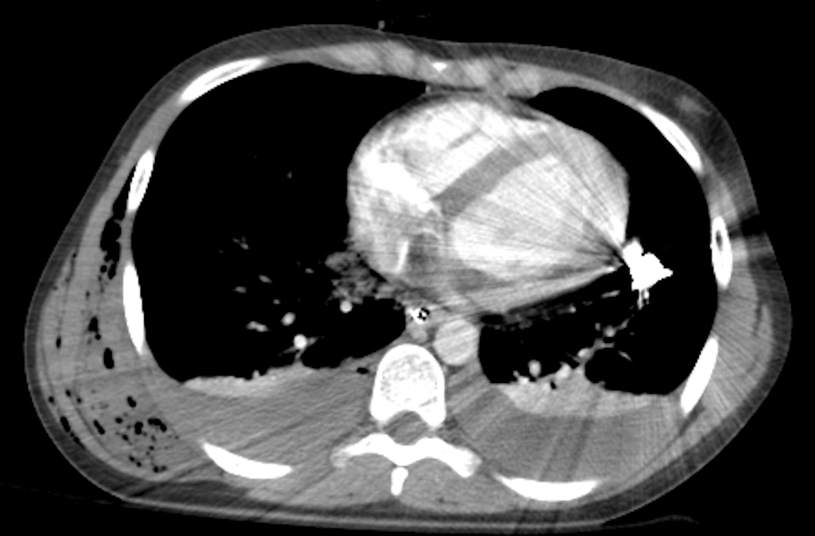

Young adult stab to left chest. BP 116/64, HR 108. Alert, talking. FAST exam done. #POCUS #FOAMed #FOAMus #FOAMcc #MedEd #echofirst @ACEP_EUS @PhilipsPOCUS @cianmcdermott @grepmeded @jminardi21 @HeyDrNik @ten8suited @tomkehrl @thepocusatlas

Has Large echogenic hemopericardium. Amazing that patient is awake, alert, talking and has BP 116/64 despite rapid accumulation of such a large amount of pericardial blood. To OR emergently-did well.